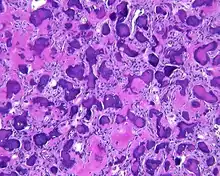

Pathology findings

By microscopic evaluation, the tumors are composed of a variably cellular stroma make up of spindled to stellate fibroblast-like cells. Within this stroma, are numerous small, rounded, mineralized collagenous ossicles and immature osteoid. Many times the curved-shaped bone fragments have a collagenous rim around them. Ossicles may fuse to form much large mineralizations. Cementum-like psammomatous bodies (cementicles) may also be present. Osteoblastic rimming is not uncommon. Occasionally, giant cells and even mitoses are seen.[1][3]